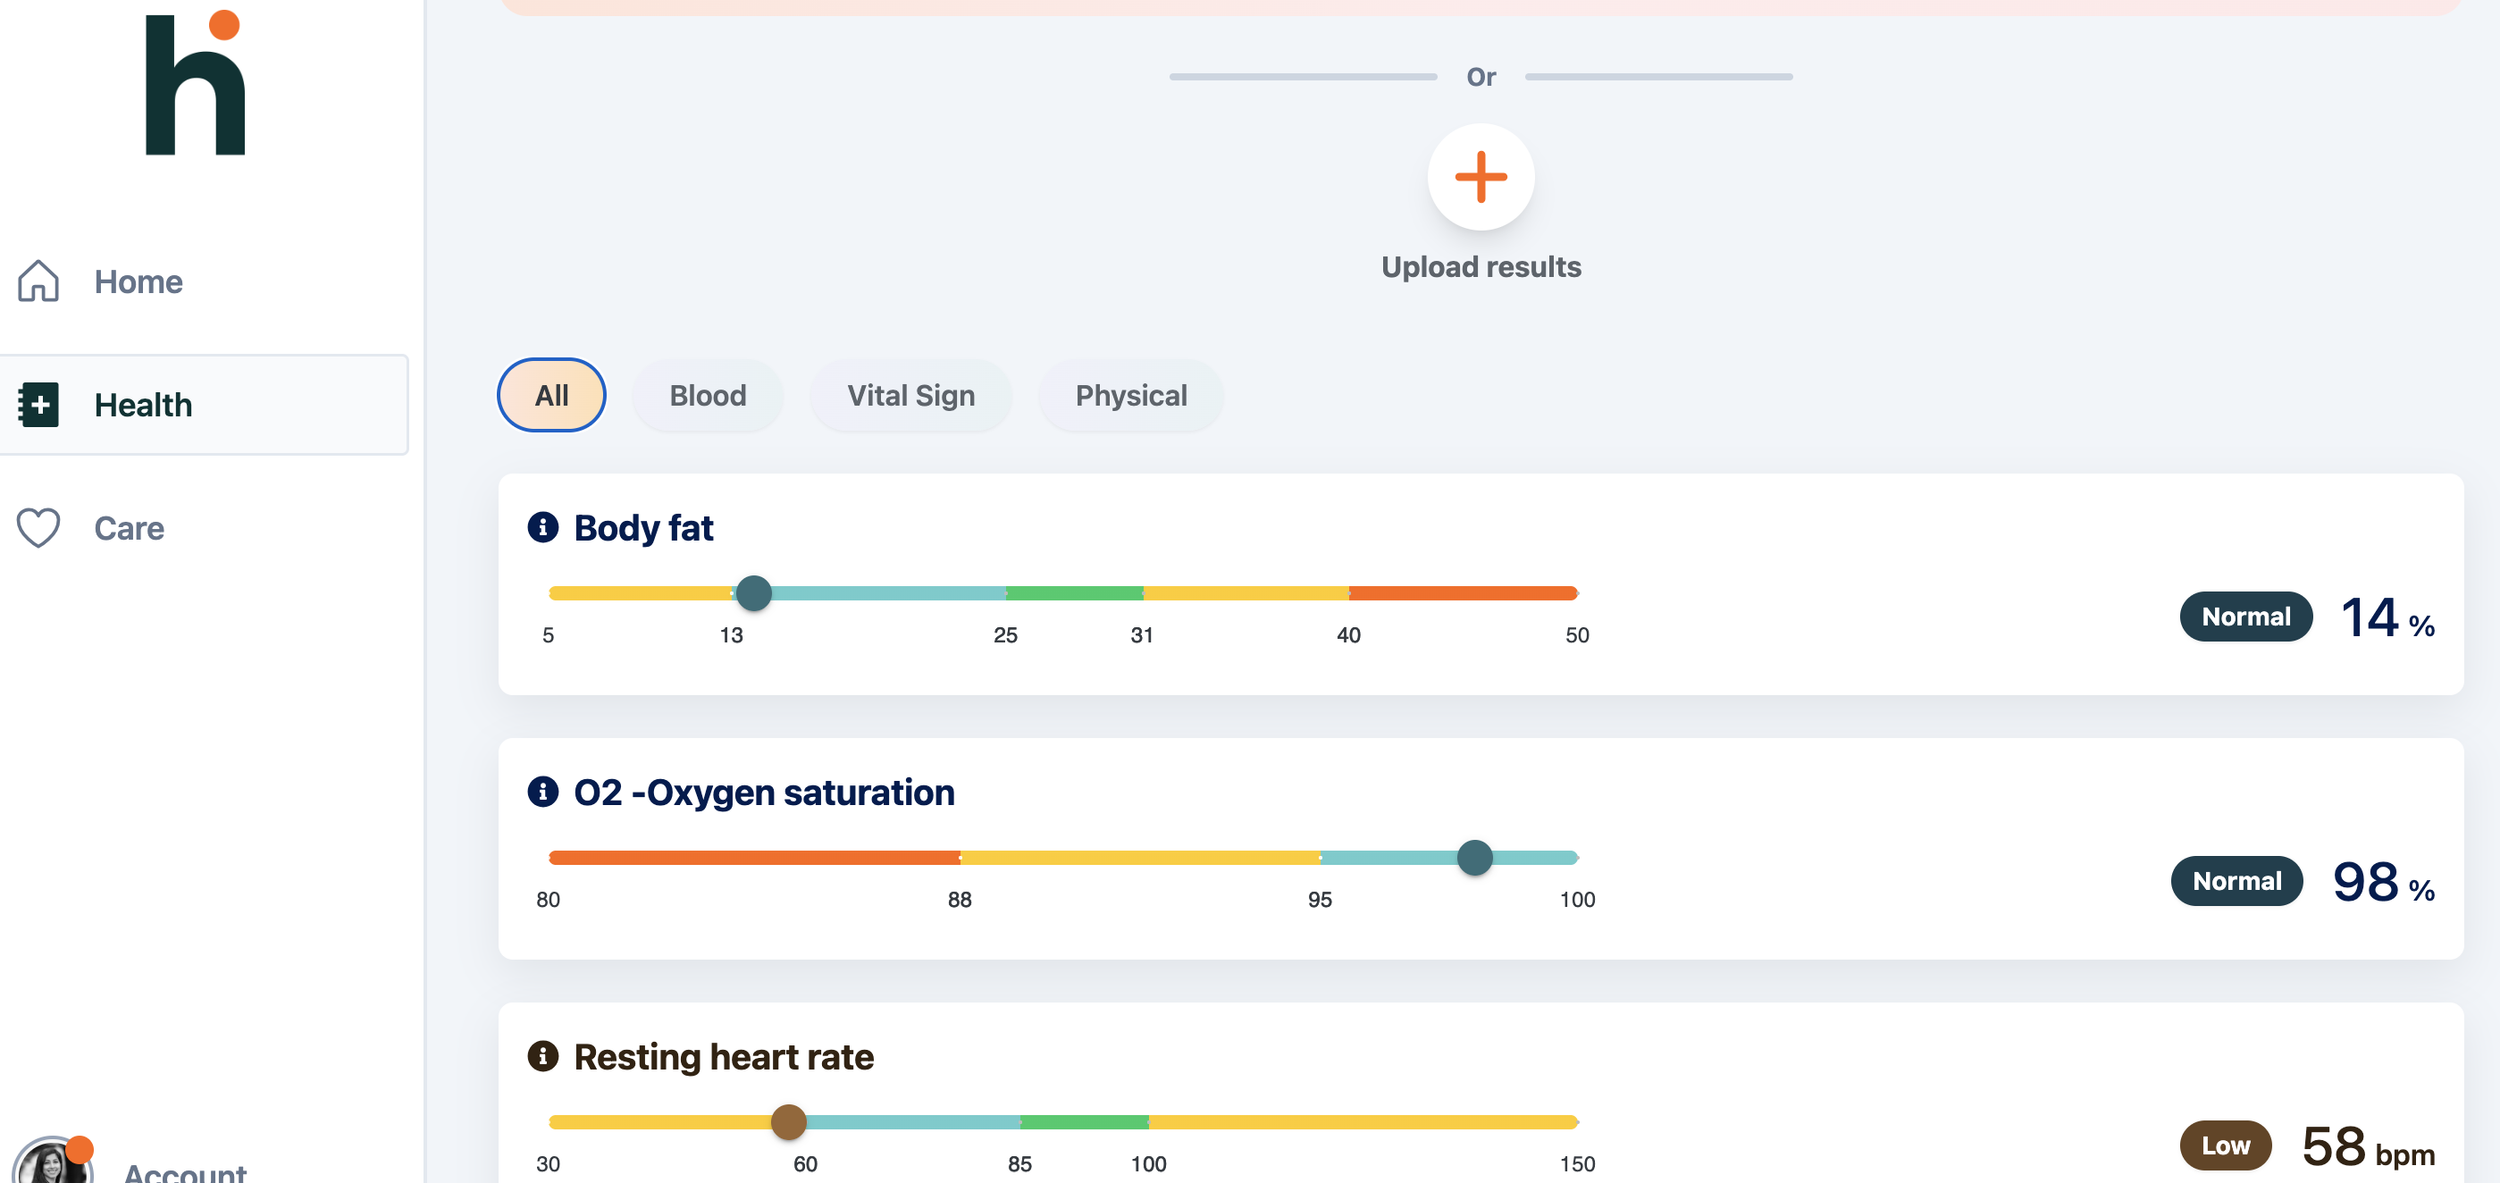

Join the LIV community @ Helfy

To ensure the highest standard of care, all LIV bookings, health plans, and secure payments are managed through our dedicated partner platform, Helfy.

Your Personal Longevity Portal

Once you book, you’ll gain exclusive access to the Helfy App

Your Longevity Data in One Place

Real-Time Progress Tracking